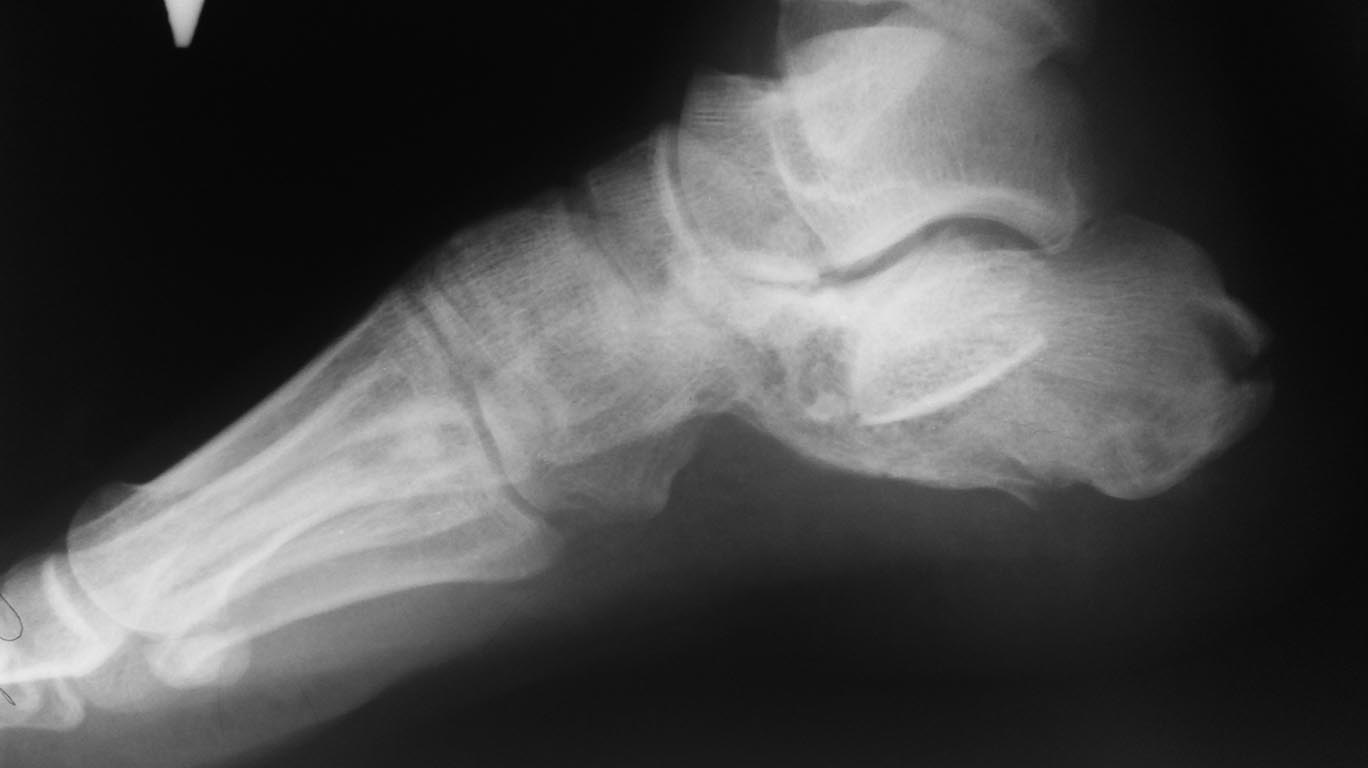

Имя     : 20170317_184644.jpg

Тип     : image/jpeg

Url     : http://weborto.net:8080/pipermail/ortho/attachments/20170320/7e16afb9/attachment-0003.jpg